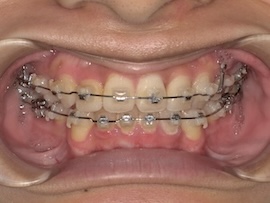

前回から1ヶ月後の歯並びはこんな感じです。

そこから1ヶ月後、

さらに1ヶ月後、